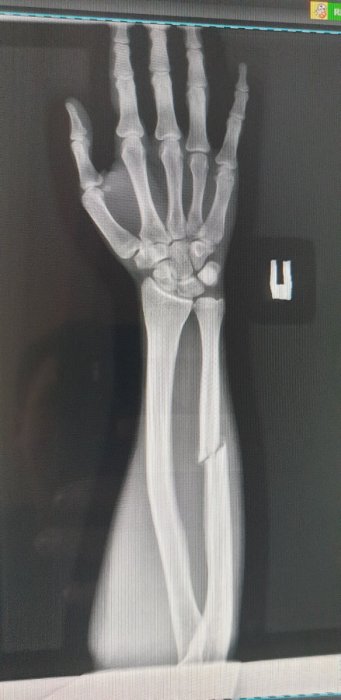

на   снимке-  рука.

имеет  место   перелом лучевой   кости со  смещением.

левая стопа. это   рука,  конечность,   верно. Сильный ушиб, возможно с трещиной, но без перелома

Нога , голень   это  конечность,   но  рука...нижняя треть , голеностоп , перелома не ощущается, вывих или растяжение